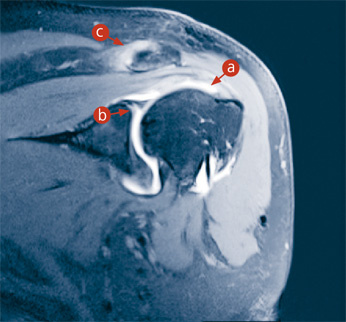

Das vorliegende Bild zeigt die linke Schulter in einem 3-Tesla-Magnetfeld. Der 56-jährige Patient ist auf die ausgedrehte Schulter gefallen: Nach Füllung des Gelenkraums mit 15 ml Kontrastmittel wird ein Teilriss der Supraspinatussehne (a) sichtbar sowie ein feiner Riss der Knorpellippe am oberen Pfannenrand (SLAP-Läsion; b) an der Verankerung der langen Bizepssehne. Zusätzlich besteht eine Quetschung des AC-Gelenks (Acromio-Clavicular-Gelenks; c).

Speziell die Abklärung der Gelenke hat in den letzten Jahren eine enorme Revolution in der Bildgebung erfahren. Die Einführung starker Magnete in der Grössenordnung von 3 Tesla – die Einheit Tesla umschreibt die Magnetfeldstärke und entspricht dem 100 000-fachen der Erdanziehungskraft – ermöglicht heute die Beurteilung von Knorpel-Sehnen-Übergängen und die Darstellung feiner Sehnenrisse (Abb. 1). Dies erlaubt ein genaues Auswahlverfahren der geeigneten Therapie für den Patienten. Nicht immer ist eine Operation oder eine Gelenkspiegelung (Arthroskopie) nötig, wenn die genauen Verletzungen mittels bildgebender Verfahren bekannt sind. Bei einzelnen Gelenken, wie beispielsweise dem Knie, reicht die Bildgebung aus, um ohne zusätzliche Kontrastmittel eine exakte Diagnose zu stellen.

Bei komplexeren Gelenken ist es jedoch häufig nötig, eine zusätzliche Aufdehnung des Gelenkinnenraums vorzunehmen, um feine Risse exakt darstellen zu können. So zum Beispiel beim Schulter-, Hand- und Hüftgelenk. Dort gibt es Verletzungen der Knorpel- und Sehnenübergänge, die nur mittels eines erhöhten Kontrasts im Gelenk sichtbar werden. Dazu wird das Gelenk mit einer feinen Nadel punktiert, und wenige Milliliter eines Kontrastmittels werden ins Gelenk eingebracht. Innerhalb der nächsten 30 Minuten kann dann die Bildgebung mittels MRI oder CT erfolgen (Abb.1). Das Kontrastmittel wird von den Patienten exzellent vertragen und in den folgenden Stunden über die Nieren vollständig ausgeschieden.

Das vorliegende Bild zeigt die linke Schulter in einem 3-Tesla-Magnetfeld. Der 56-jährige Patient ist auf die ausgedrehte Schulter gefallen: Nach Füllung des Gelenkraums mit 15 ml Kontrastmittel wird ein Teilriss der Supraspinatussehne sichtbar, ebenso ein feiner Riss der Knorpellippe am oberen Pfannenrand (SLAP-Läsion) an der Verankerung der langen Bizepssehne. Zusätzlich besteht noch eine Quetschung des AC-Gelenks (Acromio-Clavicular).